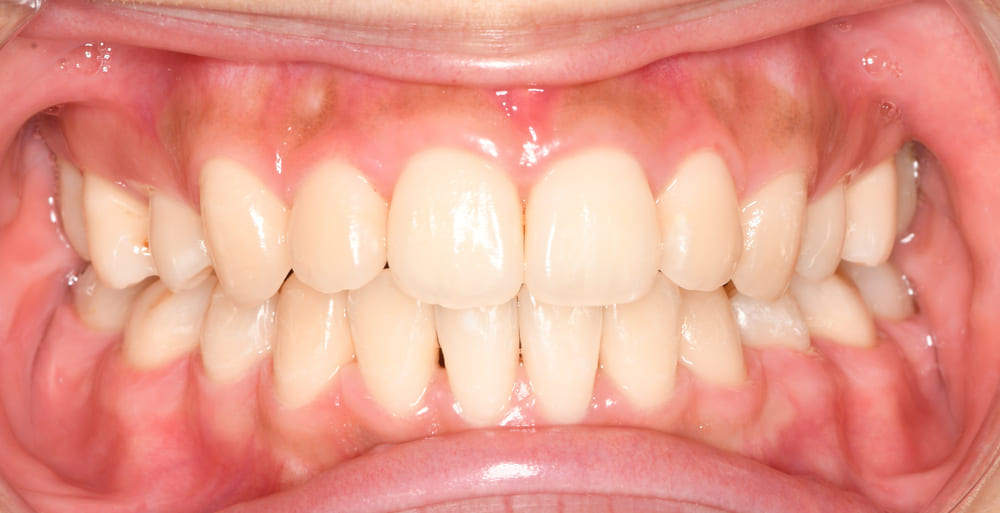

口腔内の写真です。まずは正面です。

八重歯、個々の歯の位置異常が適切に整えられていることがお分かりいただけると思います。